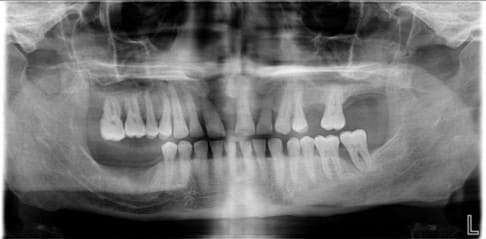

Non Annie, l'implant ne rentre pas dans la racine de 25. L'espace est étroit, mais l'implant est bien centré (voir Rx jointe).

En ce qui concerne les antagonistes, la 37 est + solide qu'il n'y parait à la Rx malgré une petite perte osseuse mésiale. J'ai réalisé un bridge 35/36/37 pendant l'ostéointégration. (l'effondrement de la crête ne permettant pas la pose d’un implant/36).

Carole, je prendrai un pano que je posterai le jour du retrait des points. Mais je ne pense pas que ça t’informe plus par rapport à la 1ère Rx.

la pano numéro un est la radio initiale.

sur la pano 2, on voit le patient après traitement paro par ma consoeur, et la pose par votre serviteur de deux implants. le résultat du traitement paro est particulièrement visible sur la dent 37.

ensuite, on perd le patient de vue un certain temps.

on le revoit aujourd'hui. progression des lésions parodontales.

quant aux implants, je vous laisse juge.